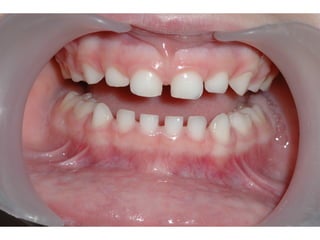

Ανωμαλίες διάπλασης της αδαμαντίνης

 Παθογεvνετικά διακρίνονται δύο μορφές

υποπλασία – μια ποσοτική ανωμαλία

της αδαμαντίνης, εντοπισμένη ή

γενικευμένη μείωση του πάχους που

οφείλεται σε διαταραχές στην εκκριτική

φάση

 Υπενασβεστίωση – διαταραχές κατά το

στάδιο της ενασβεστίωσης, έτσι τμήματα

της αδαμαντίνης αποσπώνται γρήγορα

Υπενασβεστίωση γομφίων και τομέων

 Επιπολασμός 4 - 25% ανάλογα με τον

πληθυσμό που εξετάζεται

 Ο αριθμός των δοντιών ποικίλει από ένα

έως τέσσερα

 Ο βαθμός προσβολής ποικίλει από ελαφρώς

έως βαριά

Ανωμαλίες διάπλασης τηςαδαμαντίνης  Παθογεvνετικά διακρίνονται δύο μορφές υποπλασία – μια ποσοτική ανωμαλία της αδαμαντίνης, εντοπισμένη ή γενικευμένη μείωση του πάχους που οφείλεται σε διαταραχές στην εκκριτική φάση  Υπενασβεστίωση – διαταραχές κατά το στάδιο της ενασβεστίωσης, έτσι τμήματα της αδαμαντίνης αποσπώνται γρήγορα

Υπενασβεστίωση γομφίων καιτομέων  Επιπολασμός 4 - 25% ανάλογα με τον πληθυσμό που εξετάζεται  Ο αριθμός των δοντιών ποικίλει από ένα έως τέσσερα  Ο βαθμός προσβολής ποικίλει από ελαφρώς έως βαριά